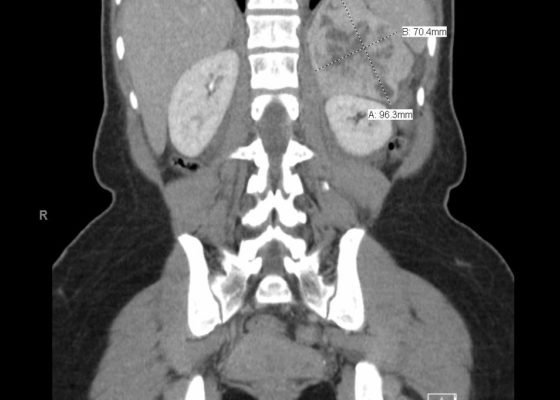

The Elusive Pheo: A Case Report of Pheochromocytoma in the Emergency Department

DOI: https://doi.org/10.21980/J8KW63ED work-up: BMP within normal limits (WNL), white blood cell (WBC) 27.4, ECG showed sinus tachycardia, nonspecific ST segment abnormalities, BNP and troponin were within normal limits, HR 146 beats/minute, CT abdomen/pelvis showed a 10-cm-heterogenous enhancing left adrenal mass (anterior-posterior view [shown in red], lateral view [shown in blue]).